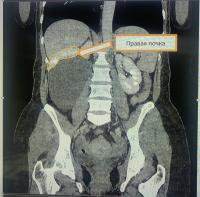

В урологическое отделение Коломенской больницы поступила 52-летняя пациентка с сильными болями в правой половине живота. При пальпации врачи обнаружили значительное по размерам новообразование, а при проведении компьютерной томографии была выявлена гигантская киста правой почки размером 17 х 11,5 см, занимавшая практически половину брюшной полости. Из-за своих размеров новообразование зажало и деформировало правую почку.